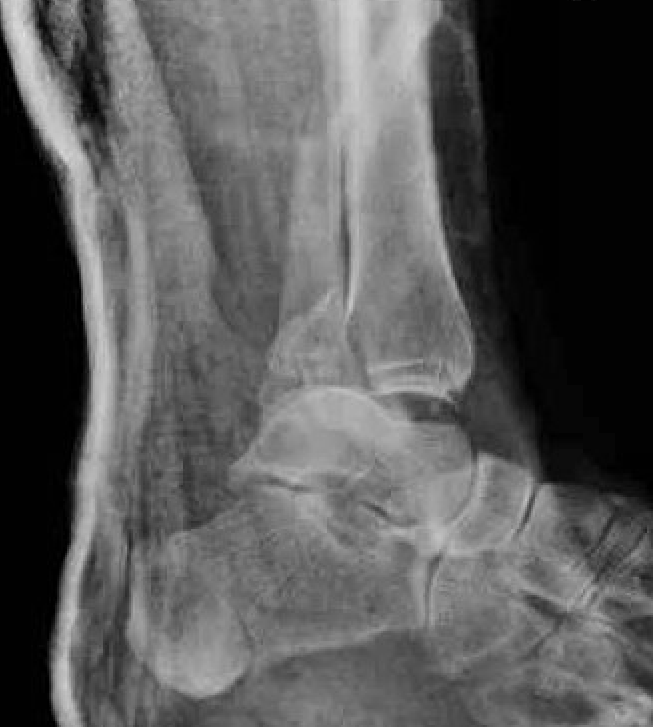

Dislocated ankle joint with large posterior malleolus

Articular incongruency

Posterior malleolus and syndesmotic injury